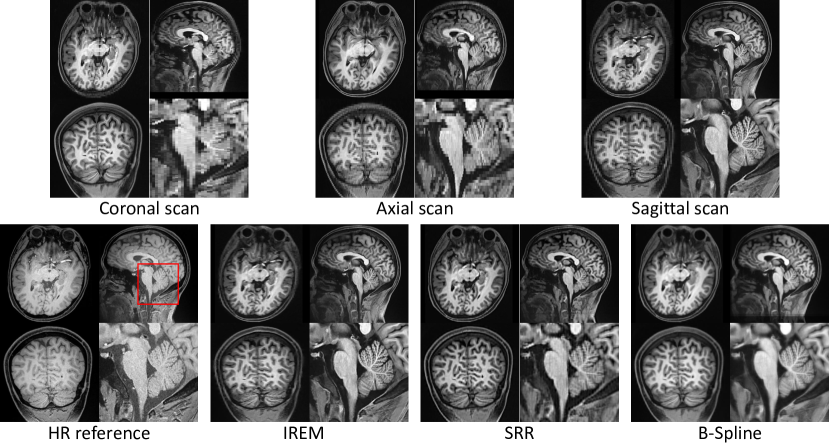

Refer to caption

Figure 6: Results of B-spline interpolation, SRR [4], and IREM on dataset #C.

3.3.3 Performance in real data collection protocol.

Figure 6 shows the results of the three methods on dataset #C. All MISR algorithms are conducted after a unique image spatial normalization step. Comparing with IREM, the image built from B-Spline is more blurry and SRR [4] yields an image with artifacts. As indicated in the enlarged part, the image built from IREM achieves equivalent qualitative image details comparing with the HR reference in the cerebellum, which is one of the most complicated anatomy in human brain. Besides, benefitting from the multiple anisotropic thick slice scanning strategy, the SNR in each voxel of the LR image stack is about 16 times (definition and computational detail of SNR can be found in [18]) higher than that in the reference HR image. Thus the image contrast between white matter and gray matter in the reconstructed image is better than that in the reference HR image. The result suggests that IREM is a more effective and reasonable pipeline to achieve high-quality HR image comparing with scanning directly an isotropic HR image.